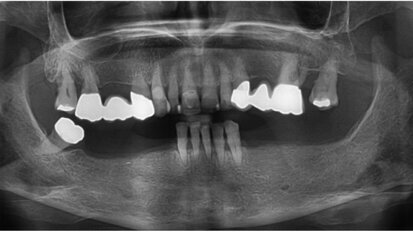

Management of iatrogenic pulpal floor perforation in a mandibular molar with MTA and PRF

This was a challenging case with the combined issues of a failed root canal therapy and an iatrogenic perforation of the floor of the pulp chamber. Though ...